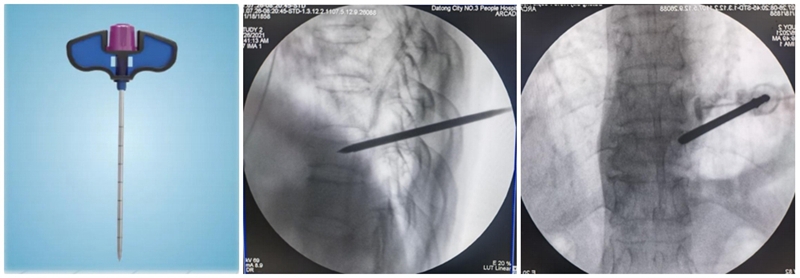

(1)定位与穿刺:透视下确定伤椎椎弓根外缘上1/3 入路点及伤椎上终板或下终板方向并做好标记。由于穿刺容错率高,穿刺针(4. 2 mm)不用过度内倾,不必苛求针尖在椎体内侧壁、后壁位置,穿刺针从椎弓根外缘沿椎弓根方向缓慢穿刺入椎体即可,针尖务必穿刺入椎体后1/3。

(2)弯角导丝开腔:弯角骨钻开腔器械刺入椎体时,注意开腔工具手柄与伤椎终板平行,不要强行开腔,多透视侧位,否则弯导丝可能穿破终板,导致医源性骨水泥渗漏。C形臂X线机正位透视下,导丝到达椎体对侧椎弓根处即可。